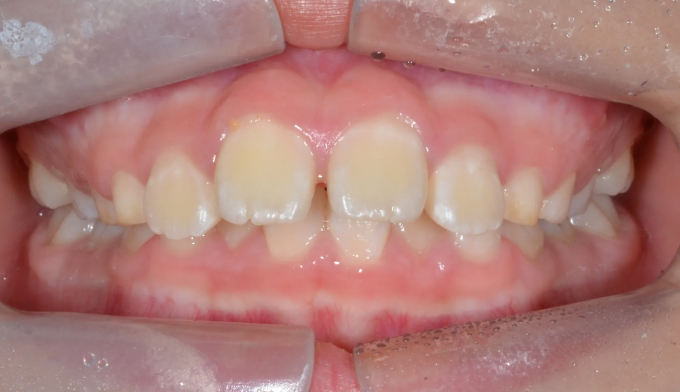

돌출입

소아

2025.02.11